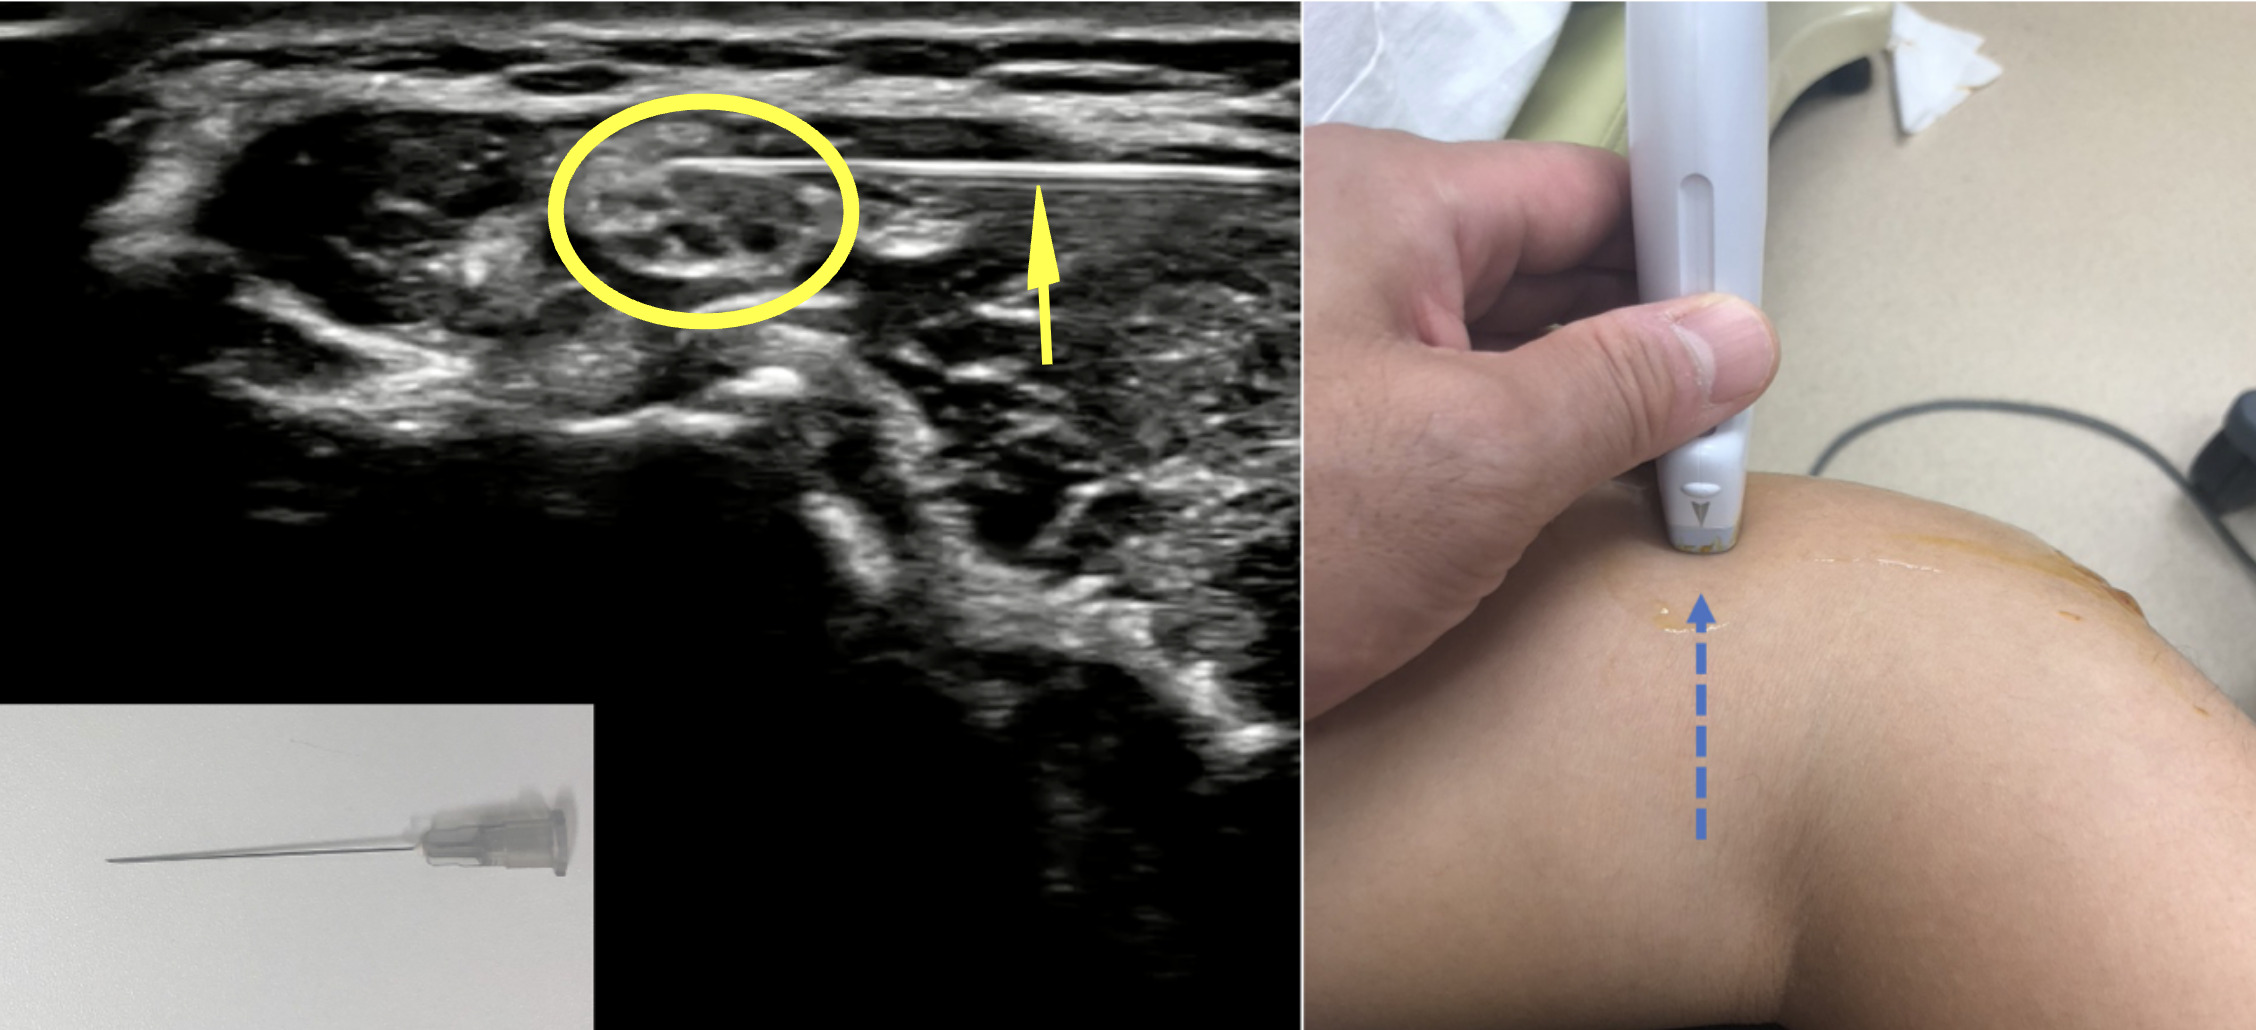

~尺骨神経障害へのエコー診断下の痛みの改善例~

スポーツ整形外科において超音波診療機器(以下エコー)が非常に有効です。例えば肘の痛みです。レントゲン、CT、MRなど各種異常所見がないにも関わらず、圧痛があり(無い場合もあります)、プレーに支障がある場合に尺骨神経障害の可能性があります。もちろんその診断には各種身体所見を詳細に確認し判断します。安静や投薬が一般的な治療でありますが、診察所見やスポーツ活動の状況によっては《尺骨神経ハイドロリリース》を行います。

エコーを使用することで尺骨神経が描出でき、安全に神経周囲に細い針で主に生理食塩水を中注入することで痛みの改善につながる症例を経験します。生理食塩水を筋間や神経周囲に注入することで組織の滑走の改善、酸素状態の変化、血流の改善などが得られ疼痛の改善や動作の改善が得られることが報告されています。

黄色丸:ブドウの房のような像が神経の断面

黄色矢印:白い線が注射針

青の点状矢印:針のすすめる方向(画像は肘関節の内側にエコーを当てている状態)